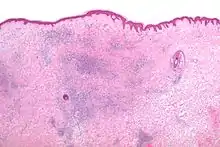

Microscopic appearance

The histomorphologic appearance of insect bites is usually characterized by a wedge-shaped superficial dermal perivascular infiltrate consisting of abundant lymphocytes and scattered eosinophils. This appearance is non-specific, i.e. it may be seen in a number of conditions including:[5]

- Drug reactions,

- Urticarial reactions,

- Prevesicular early stage of bullous pemphigoid, and

- HIV related dermatoses.